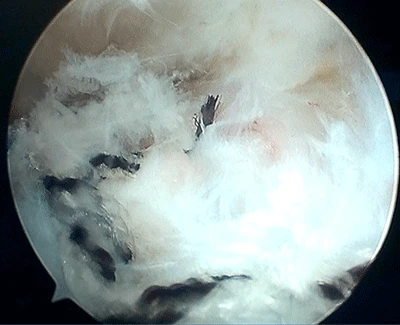

Vista de la cirugía desde la cámara artroscópica